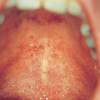

Glossitis rhomboidea mediana

– Keele keskosa arengus osalev tuberculum impar võib keele keskjoonel jääda nähtavaks punetava, sileda ja rombitaolise kõrgendiku või lohuna. – Muutus on ohutu, kuid seda tuleb eristada keele kasvajatest (vähegi...